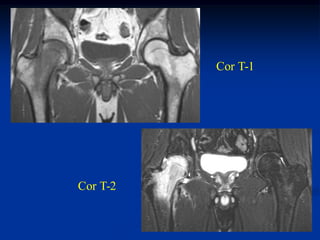

Case #936.1                Hodgkin’s lymphoma

28 year old male with hip pain for past 3 months

Bone scan

Cor T-1   T-2   Gad

Axial T-1   T-2

gad